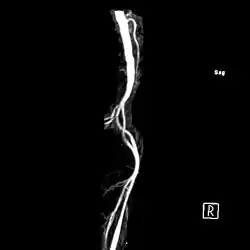

| Магнітно-резонансна ангіографія, на якій видно артерію Адамкевича, що відходить від аорти. Див. мала судина зверху праворуч. Вигляд з правого боку. | |